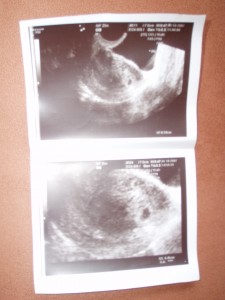

Maminka byla v práci nervozní, protože odpoledne šla k paní doktorce.Paní doktorka udělala mamince vyšetření a ultrazvuk, kde mohla vidět gestační váček, ale ještě nebylo vidět srdíčko, byla právě v 5.tt a já jsem měřil 4,5mm

Obrazek